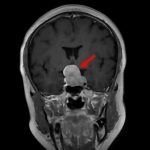

断層撮影

手術前2